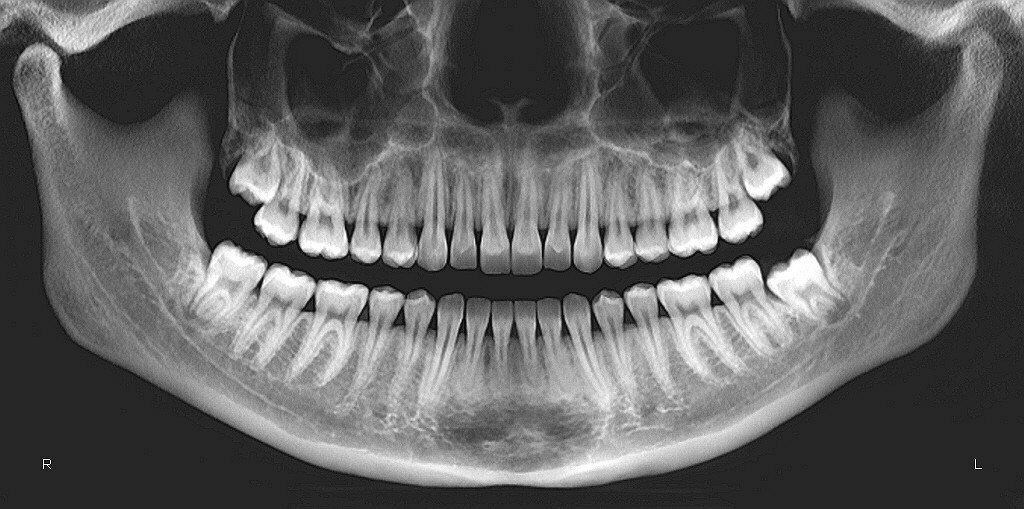

Ортопантомограмма (ОПТГ) — панорамный рентгеновский снимок зубов

Ортопантомограмма — это панорамный рентген-снимок обеих челюстей. Аппарат вращается вокруг головы пациента и создает единое изображение всей зубочелюстной системы.

В отличие от прицельных снимков, здесь видна общая картина: положение зубов, состояние корней, уровень костной ткани и скрытые процессы.

ОПТГ — это двухмерное изображение. Оно дает общий обзор и подходит для первичной диагностики.